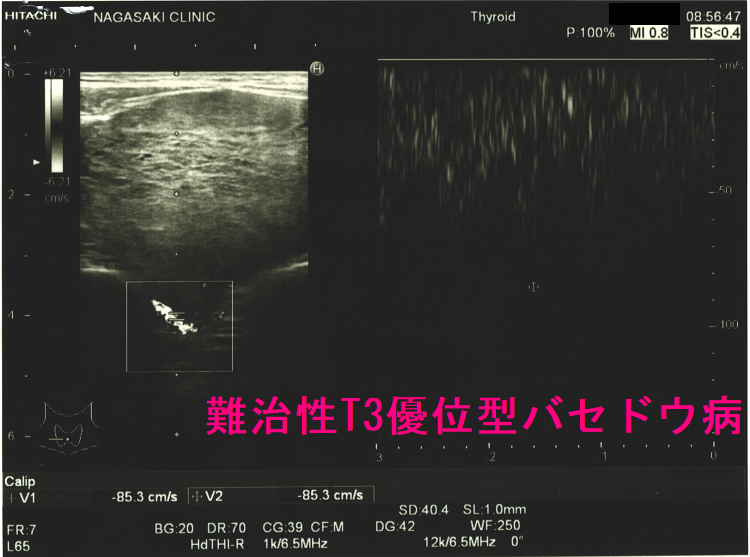

ケース① 下甲状腺動脈血流速度(ITA-PSV)は異常高値

T3優位型バセドウ病 超音波(エコー)画像 ドプラーモード:下甲状腺動脈血流速度(ITA-PSV)は異常高値です。

T3優位型バセドウ病の異常に太い下甲状腺動脈。総頚動脈とほぼ同じ太さで、赤・青・黄が混じった乱流になっています。下甲状腺動脈血流速度(ITA-PSV)も異常に高く、186cm/sでした。

ケース④ 一度も甲状腺機能正常化したことが無く、甲状腺全摘手術に

難治性T3優位型バセドウ病 下甲状腺動脈血流速度(ITA-PSV)も高値で85.3cm/sでした。